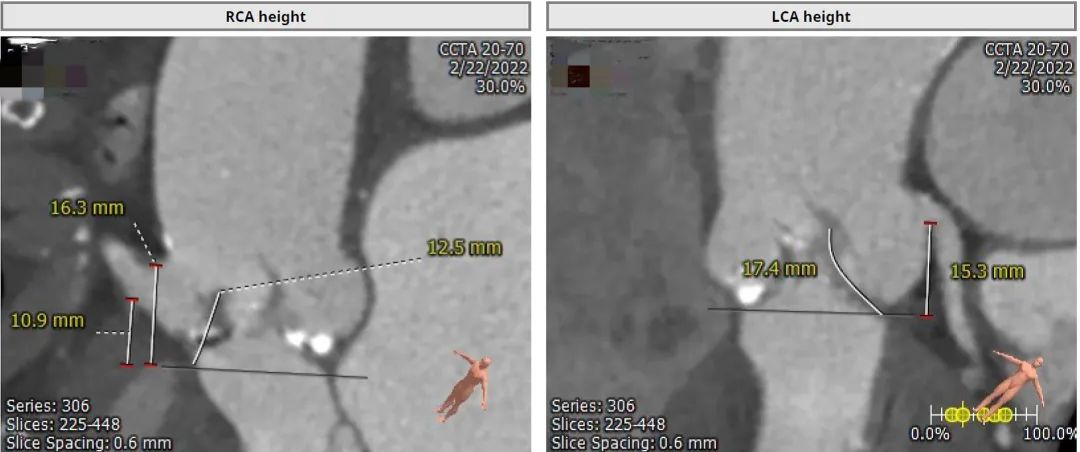

SOV 32.6×33.6mm,STJ 30.3mm,RCA 15.5mm,LCA 11mm;窦部宽大,STJ直径较宽,瓣叶冗长,提示冠脉闭塞低风险。

右侧股动脉入路平均直径5.5mm,左侧入路内径4.7mm。